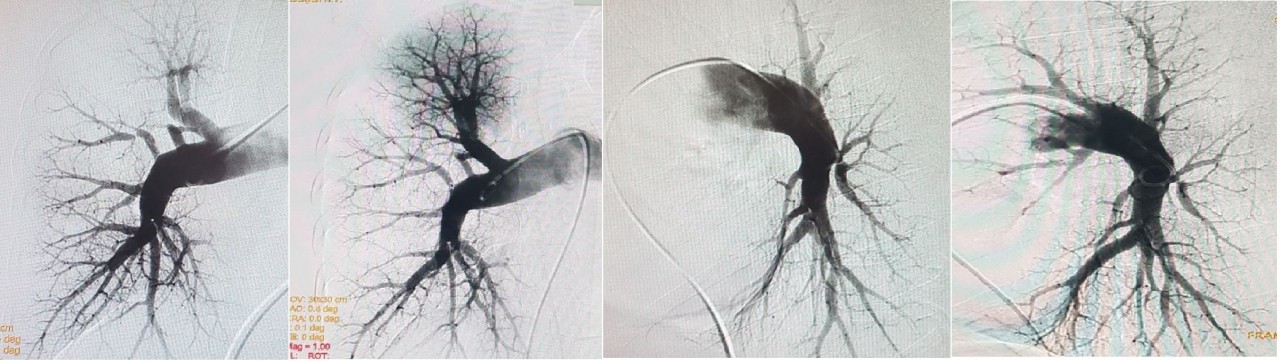

В Центре Алмазова под руководством профессора Ольги Михайловны Моисеевой сформирована команда, включающая врачей-рентгенологов, эндоваскулярных и сердечно-сосудистых хирургов, кардиологов — специалистов в области легочной гипертензии. Они ведут пациентов с ХТЭЛГ, а также изучают причины данного заболевания, разрабатывают и внедряют новые методы его лечения. Пациентка из Краснодарского края впервые была госпитализирована в Центр Алмазова в 2019 году. После подтверждения диагноза интервенционный хирург Нарек Вачаганович Марукян последовательно выполнил несколько этапов баллонной ангиопластики, в результате чего нормализовались показатели гемодинамики малого круга кровообращения. В дальнейшем больная наблюдалась в Центре Алмазова. Убедительный положительный эффект хирургического лечения хронической тромбоэмболической легочной гипертензии позволил отменить специфическую медикаментозную терапию, после чего пациентка смогла забеременеть, выносить беременность, родить и начать грудное вскармливание, не нуждаясь в дополнительной медикаментозной поддержке.

«В течение последних десяти лет мы прошли непростой путь формирования мультидисциплинарной команды ХТЭЛГ и освоили доступные на сегодня в мире методы лечения этих больных, основные из которых — это легочная тромбэндартерэктомия и баллонная ангиопластика легочной артерии. Особенностью данного случая является полная и стойкая нормализация показателей гемодинамики малого круга кровообращения на фоне эндоваскулярного лечения, что позволило пациентке не только вернуться к полноценному образу жизни, но и планировать беременность, успешная реализация которой стала возможна в условиях наблюдения мультидисциплинарной командой», — комментирует старший научный сотрудник НИО некоронарогенных заболеваний сердца Центра Алмазова к.м.н. Мария Александровна Симакова.

Таким образом, впервые в России удалось успешно спланировать беременность у пациентки с хронической тромбоэмболической легочной гипертензией после эффективного лечения с помощью метода баллонной ангиопластики легочной артерии.